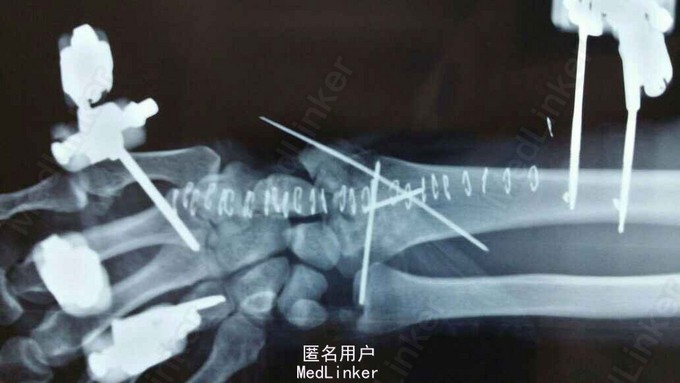

患者于2015年8月18日从高处坠落(约7米)伤及双碗,肿胀,畸形,活动受限。

双碗畸形明显,肿胀明显,可见明显皮下淤血,压痛阳性,可触及明显骨察感及骨察感,左手有明显正中神经压迫症状。

诊断:双尺桡骨远端粉碎性骨折 治疗:入院后,给予手法复位夹板固定,左手神经症状明显缓解,给予对症治疗,消肿后,于2015年8月27日行手术治疗。

请问大家,对于这种骨折是行外架+克氏针固定好,还是钢板固定好?